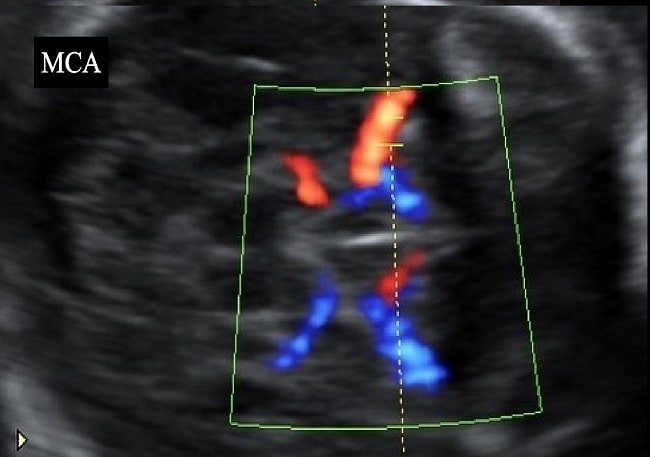

Rasio serum sFlt-1/PIGF dapat menjadi salah satu prediktor pertumbuhan janin terhambat pada kehamilan. Penggunaan rasio sFlt-1/PIGF harus di kombinasikan dengan pemeriksaan PIGF dan ultrasonografi untuk mendiagnosis IUGR.